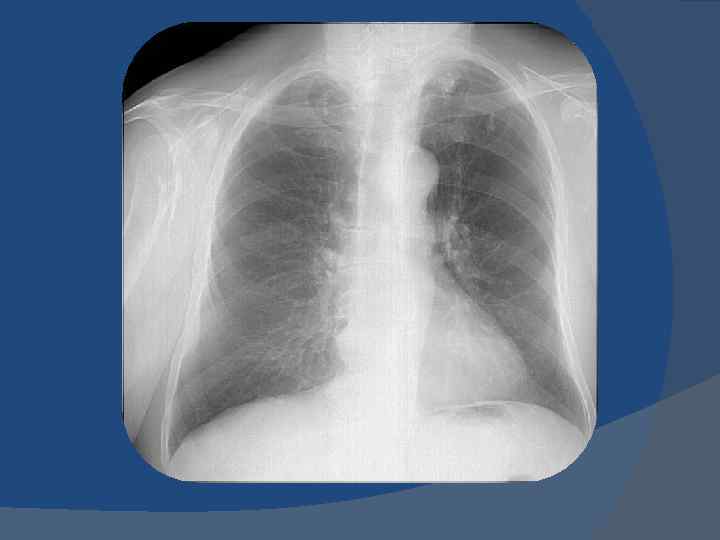

Критерии структурности корня легкого 1. Ширина легочной артерии – до 15 мм; 2. Визуализация промежуточного бронха (10 мм); 3. Сужение к периферии легочной артерии; 4. Четкие, ровные контуры легочной артерии.

Критерии структурности корня легкого 1. Четкие, ровные контуры легочной артерии. 2. Ширина легочной артерии – до 15 мм; 3. Визуализация промежуточного бронха (10 мм); 4. Сужение к периферии легочной артерии;